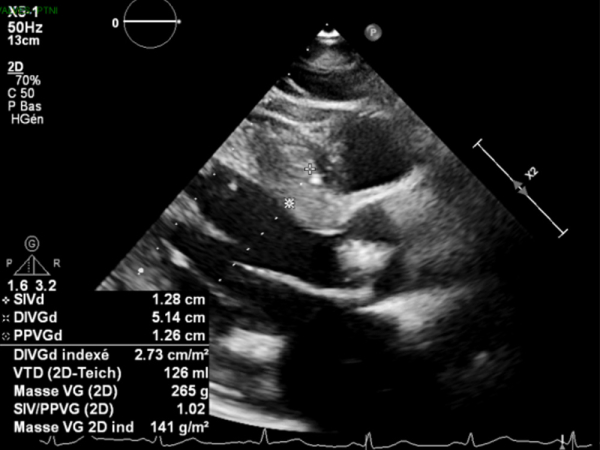

Paramètres échographiques

IRM du cœur (01/2021) évocatrice d'une amylose cardiaque

- HVG avec épaisseur septale à 19 mm

- Épaississement du septum interatrial

- Dilatation OG (25 cm²)

- VD non dilaté, hypertrophié, à fonction systolique conservée